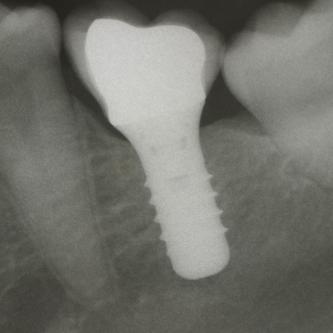

Exemple 7: Un implant au niveau de la deuxième prémolaire inférieure gauche.

Exemple 7: Le moignon vissé sur l'implant.

Exemple 7: La couronne en place

Exemple 7: vue depuis dessus